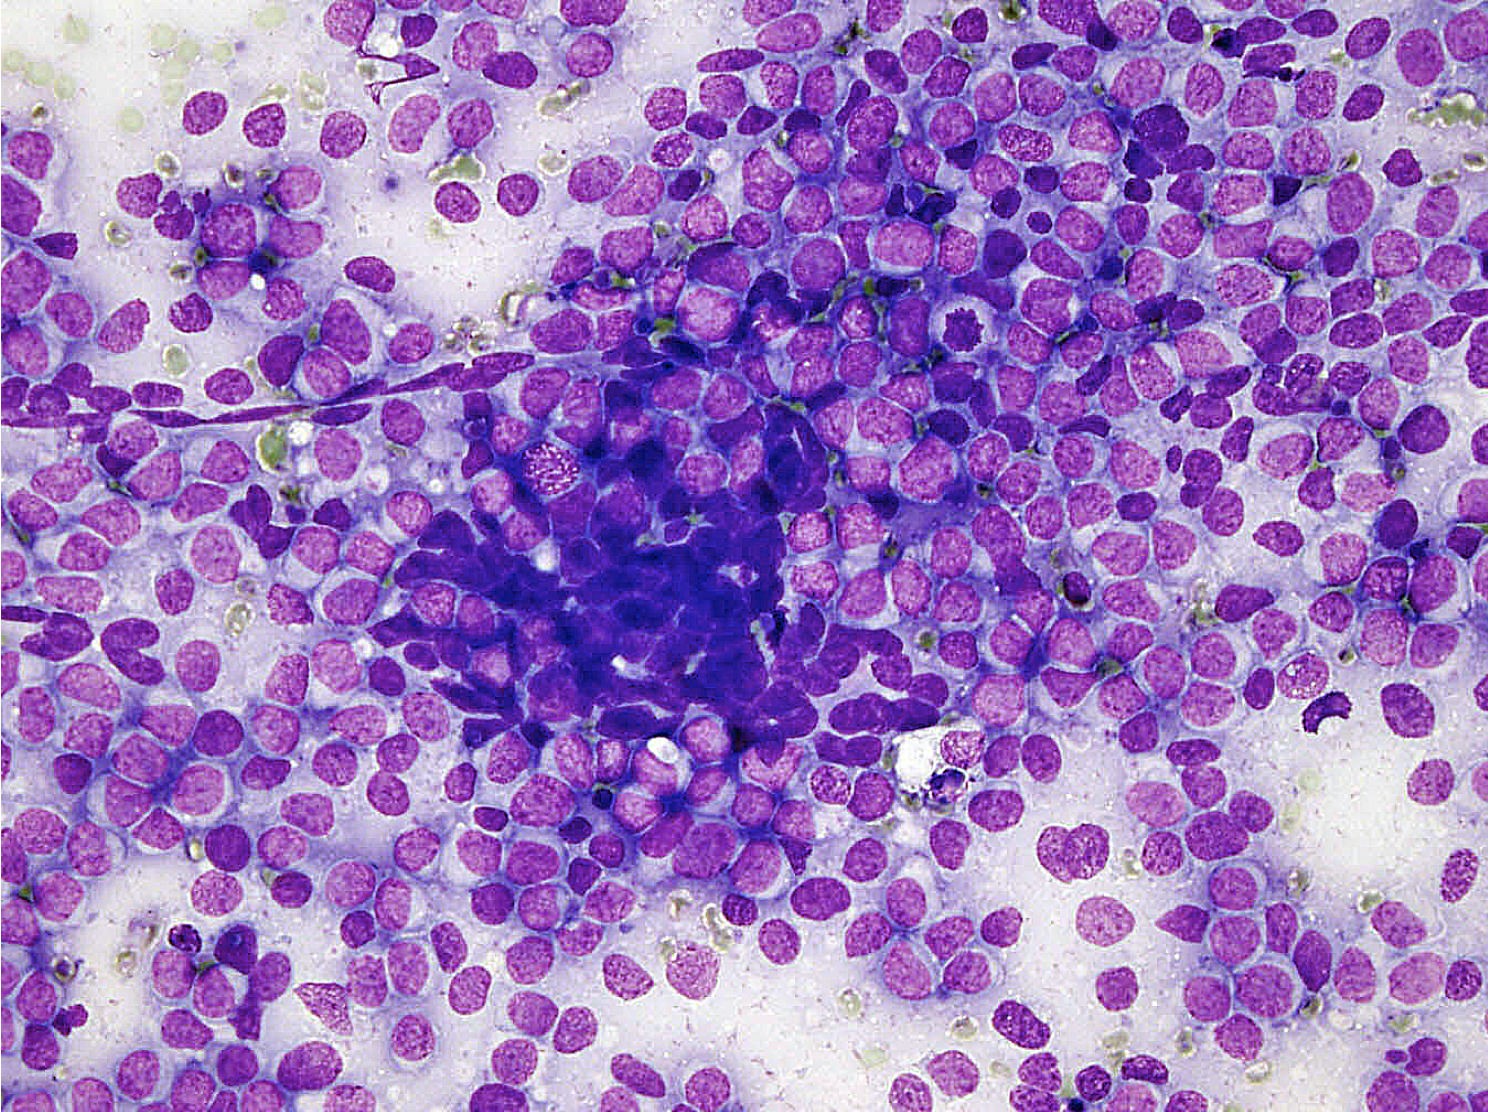

Microscopic (histologic) description

- Classical Ewing sarcoma (Virchows Arch 2009;455:397)

- Uniform small round cells

- Tumor cells 1 - 2x size of lymphocytes

- Round nuclei

- Finely stippled chromatin

- Inconspicuous nucleoli

- Scant clear to eosinophilic cytoplasm

- Indistinct cytoplasmic membranes

- Sheet-like growth pattern

- Islands separated by dense fibrous tissue

- Subset with neuroectodermal differentiation (Homer-Wright pseudorosettes)

Microscopic (histologic) images